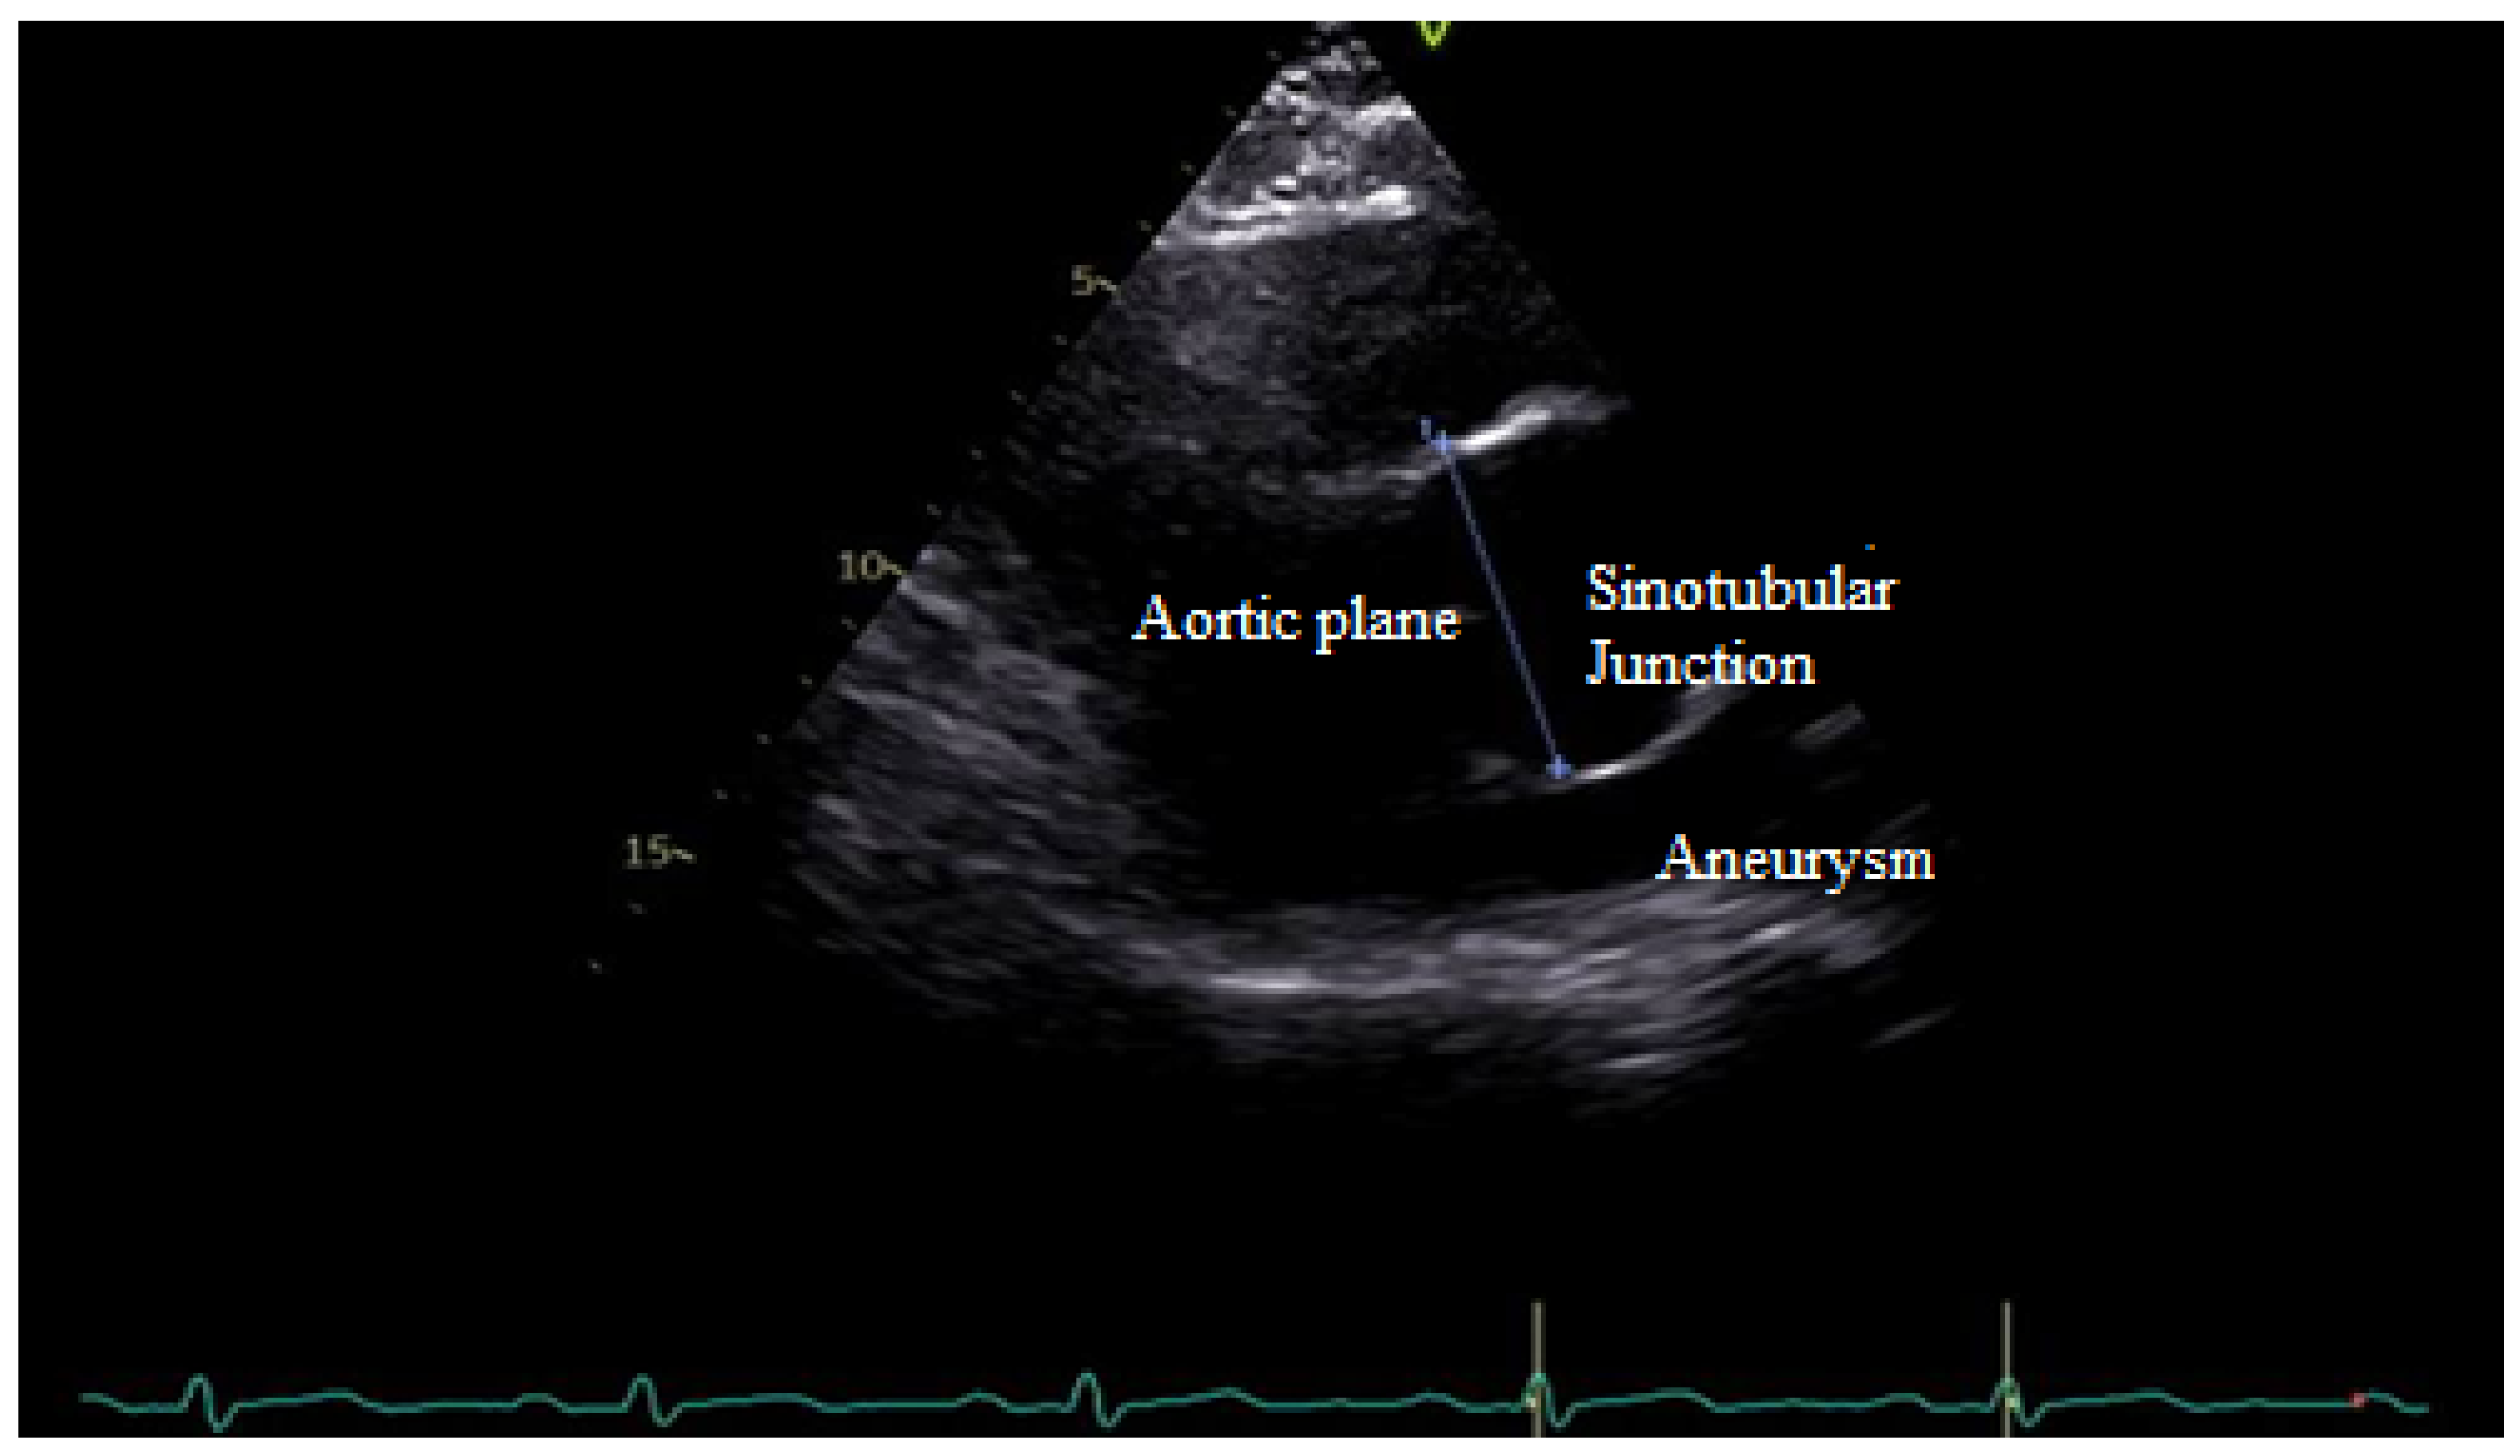

TTE determines the morphology of the valve, the connected hemorheology, the anatomical features of the root system, the diameter and the wall alteration of ascending aorta, and conditions like the aortic coarctation associated with BAV. In aortic root determination, TTE allows for measuring the sinotubular junction (STJ), especially in some aortopathy related to BAV (Figure 6).

Figure 6.

TTE shows enlargement of the sinotubular junction related to R-L cusp fusion.